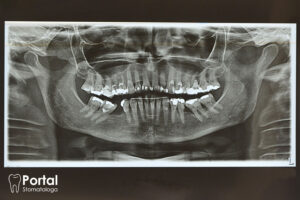

Rozwój torbieli zębopochodnych wiąże się zwykle z obecnością przetrwałych nabłonkowych wysp Malasseza, które podczas embriogenezy rozrastają się do kości. W konsekwencji zadziałania czynnika infekcyjnego następuje proliferacja przetrwałych komórek nabłonkowych i rozwój torbieli. Przyrost objętości płynu powoduje wzrost ciśnienia osmotycznego, czego efektem jest stopniowy, rozprężający wzrost zmiany. Wskutek długotrwałego bezobjawowego rozwoju, torbiele często osiągają duże rozmiary, skutkując powstawaniem rozległych ubytków kostnych, wykrywanych najczęściej przypadkowo podczas kontrolnego badania RTG.